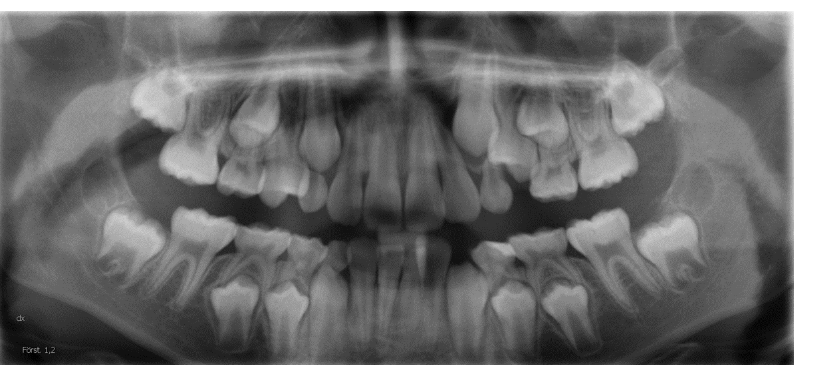

Skarpa skiktet

Det gröna fältet i mittenbilden ovan är det avbildas skarpt av maskinen. Om patienten inte är korrekt placerad i maskinen avbildas inte patienten inte optimalt.